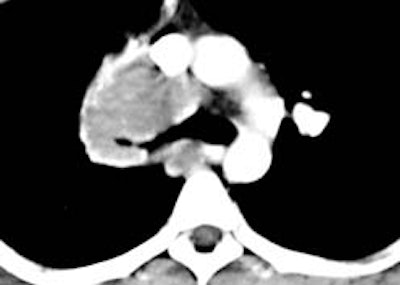

Example: The images below illustrate a case of non-small cell lung cancer which involved the carina (see drawing at right). Although this is typically considered a non-resectable T4 lesion, the tumor was treated surgically with a right carinal pneumonectomy due to the patient's young age. (Case courtsey of Dr. Douglas E. Wood, M.D.).